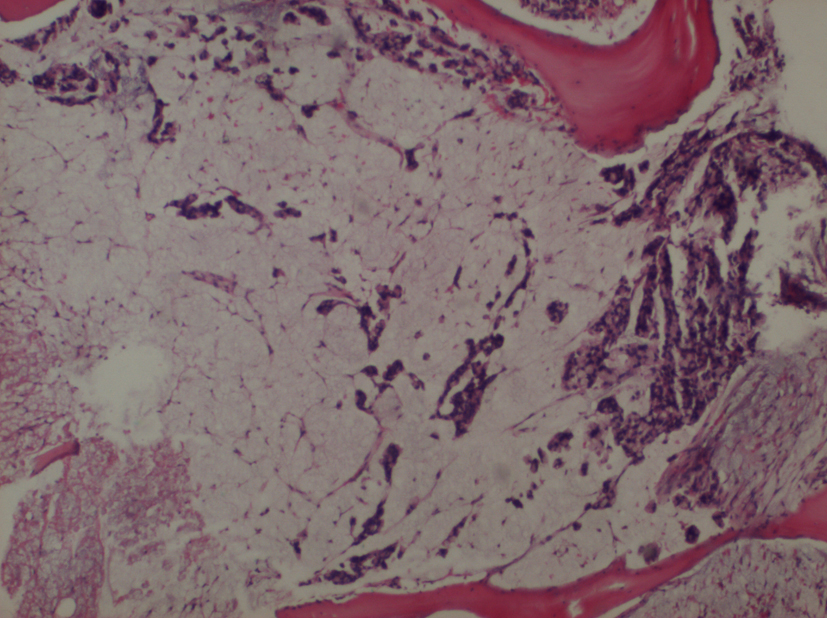

A 60-year-old female patient, with a history of cholecystectomy approximately 1 month ago and a history of using high-dose analgesics due to low back pain, has applied to the emergency service of our hospital with the complaint of rectal bleeding lasting for a week and due to general condition disorder. It has been indicated that routine tests performed at the control visit of the patient approximately 2 weeks ago were normal. In the initial tests performed at the emergency service, the following results were found: WBC: 8.6 × 109/L, Hb: 8.52 g/dL, PLT: 22 × 109/L, AST: 64 U/L, ALT: 46 U/L, LDH: 850 U/L, T. bil: 1.88 mg/dL and D. Bil: 0.79 mg/dL. Patient has been admitted to the hematology clinic with the pre-diagnosis of acute leukemia. In peripheral smear examination, no atypical cell has been observed. In abdominal ultrasonography, no pathology has been observed. Bone marrow aspiration biopsy performed has resulted as dry tap. In bone marrow imprint examination, it has been determined that cells with atypical nucleoli were compliant with distant organ metastasis causing syncytium. In bone morrow biopsy examination, there were atypic looking mucin islets and tumor cell groups occupying bone marrow spaces, among calcific bone spicules (Fig. 1). No pathology has been observed in upper endoscopic examination; in colonoscopy examination performed thereupon a massive lesion of 14 to 18 cm has been detected at rectum (Fig. 2). Mass biopsy has been observed to be consistent with rectal carcinoma. Patient, considered to have bone marrow infiltration of rectal carcinoma, has been referred to the oncology clinic for the organization of her treatment.

![]() Click for large image | Figure 1. Bone morrow biopsy examination. There were atypic looking mucin islets and tumor cell groups occupying bone marrow spaces (× 4). |